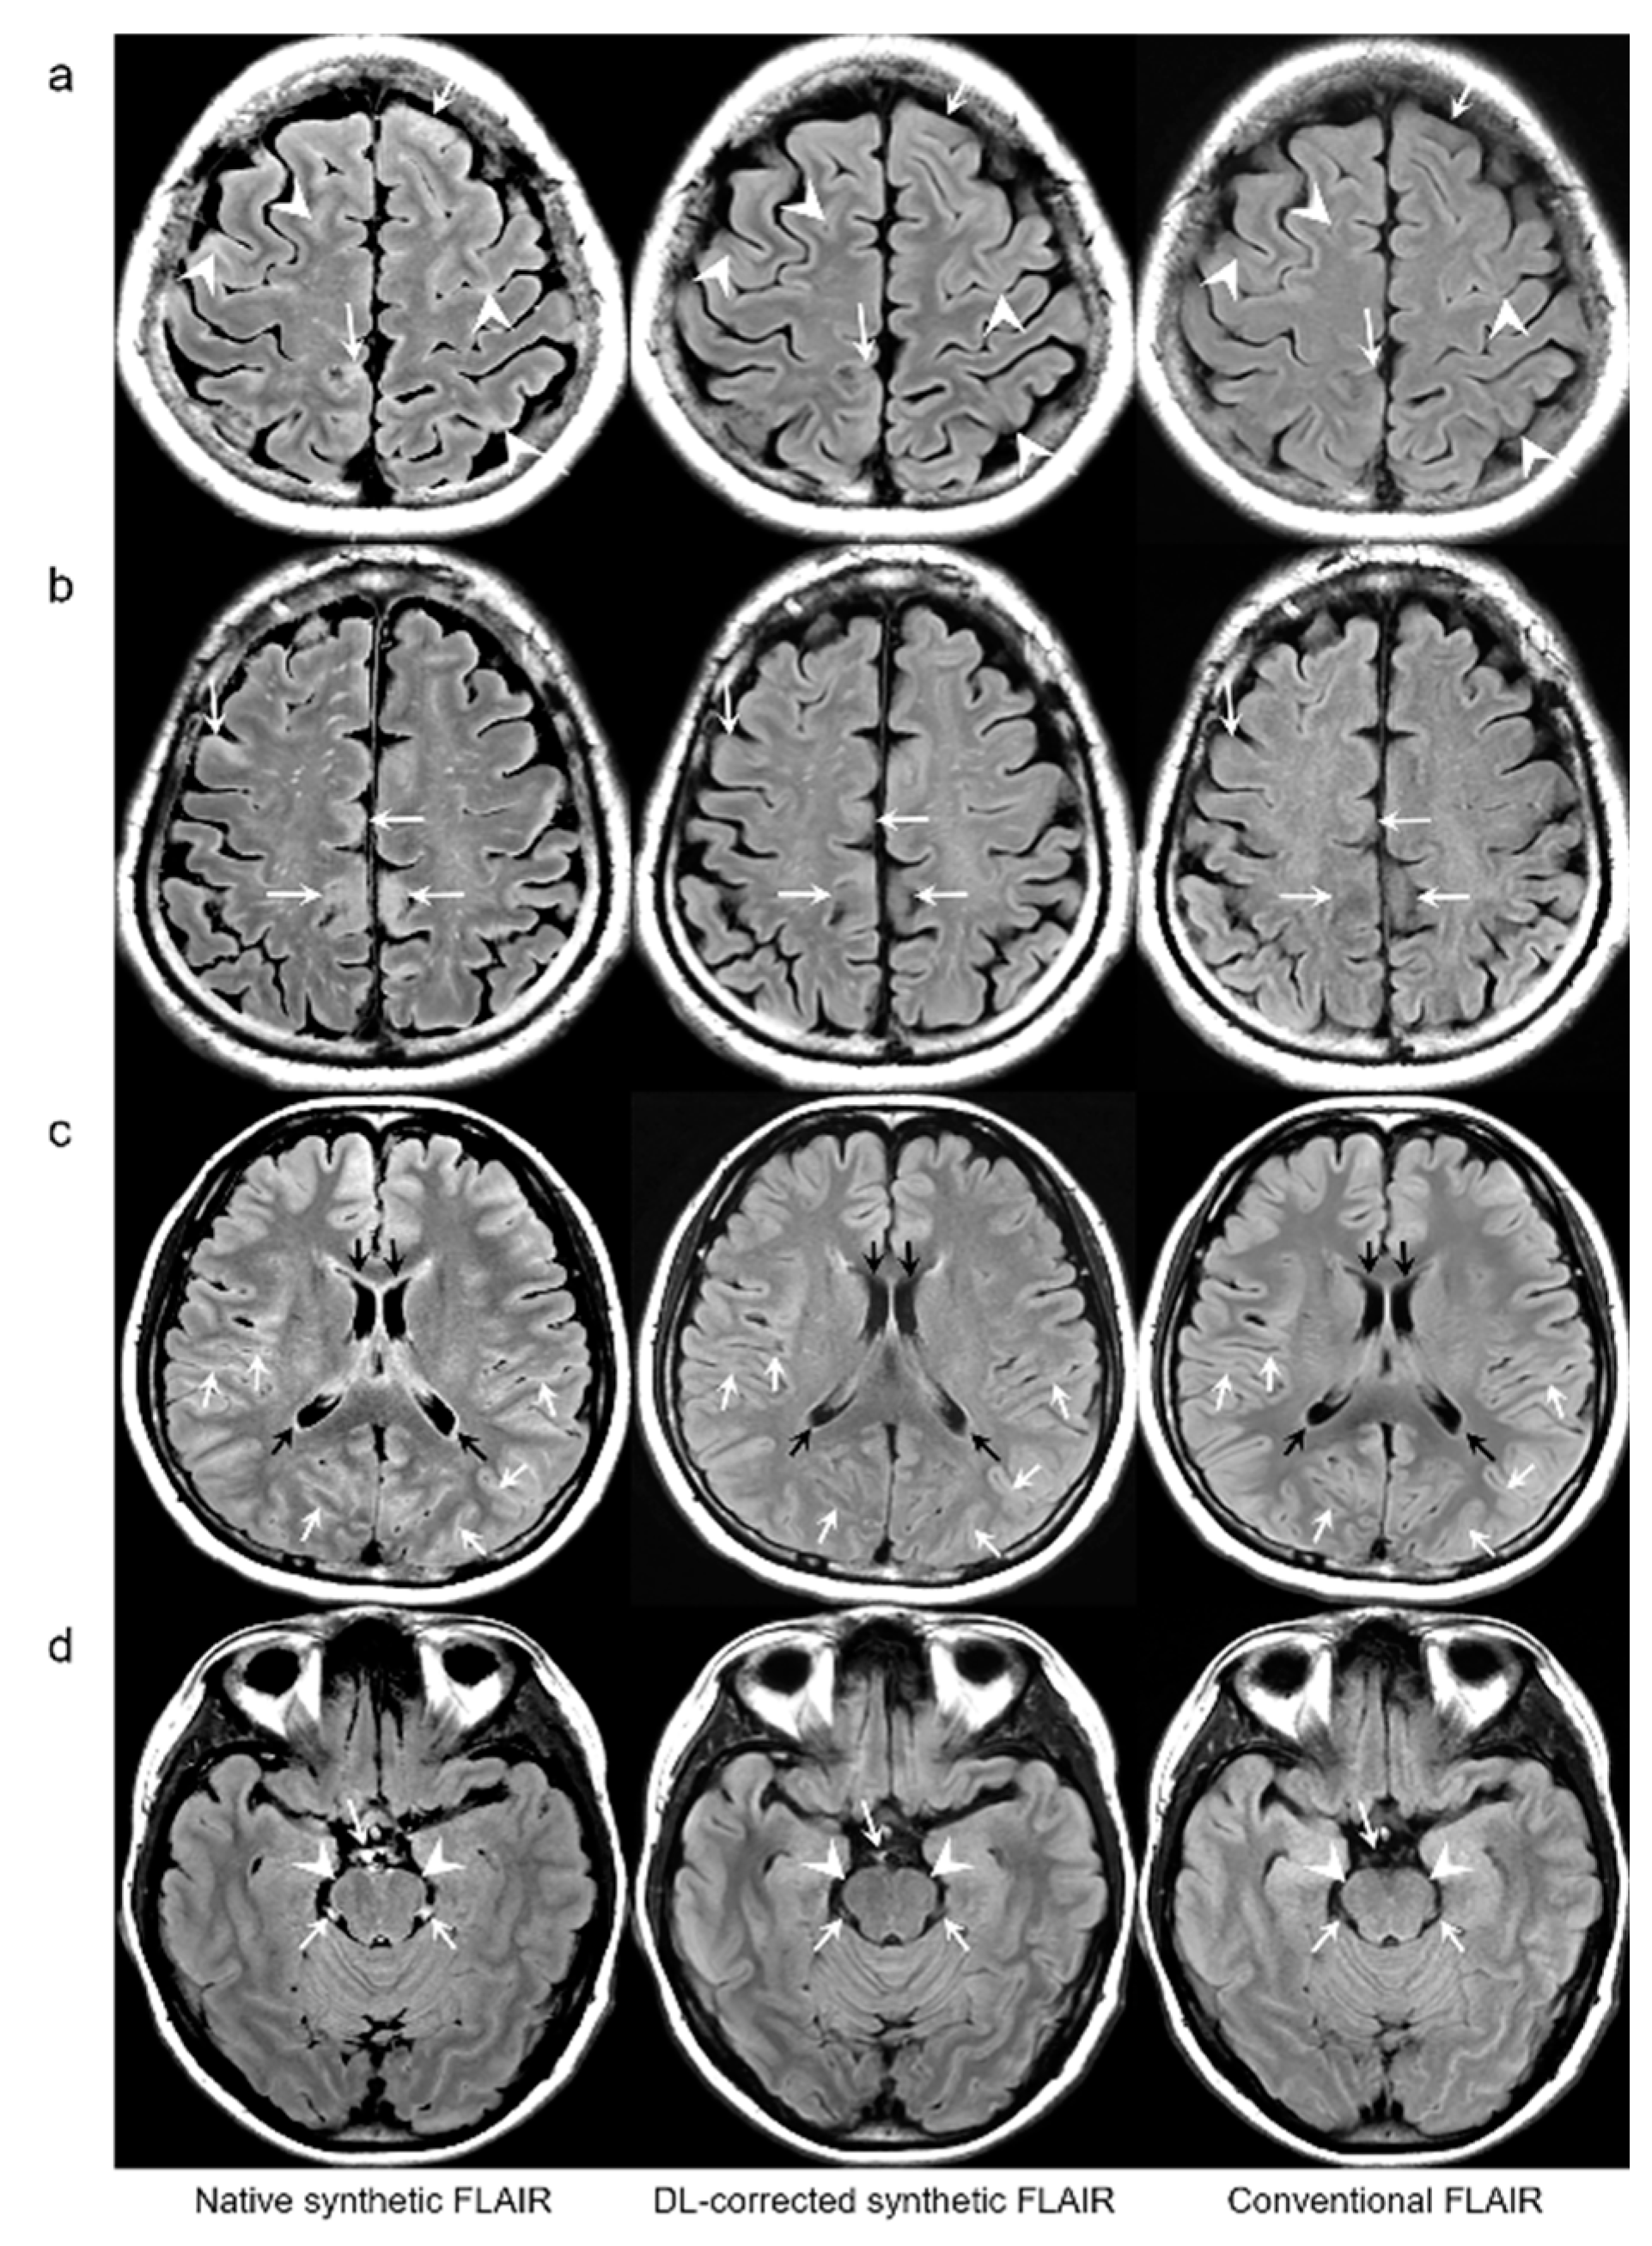

Representative examples are depicted in

Figure 2,

Figure 3,

Figure 4 and

Figure 5.

Figure 4b). The mean scores of the typical synthetic FLAIR artifacts including surface hyperintensities, granularities, or cortical swelling were identified for DL-FLAIR and native synthetic FLAIR images as follows: 1.32 ± 0.51 vs. 3.35 ± 0.68 (

p < 0.0001) (

Figure 2). In addition, other artifacts that substantially degraded the image quality, such as flow artifacts, were also improved in DL-FLAIR rather than in the native synthetic FLAIR: 1.27 ± 0.46 vs. 2.43 ± 0.72 (

p < 0.0001) (

Figure 2d).

In terms of image artifacts, the typical synthetic FLAIR artifacts were significantly improved in DL-FLAIR images (

Figure 2), which is consistent with the original work [